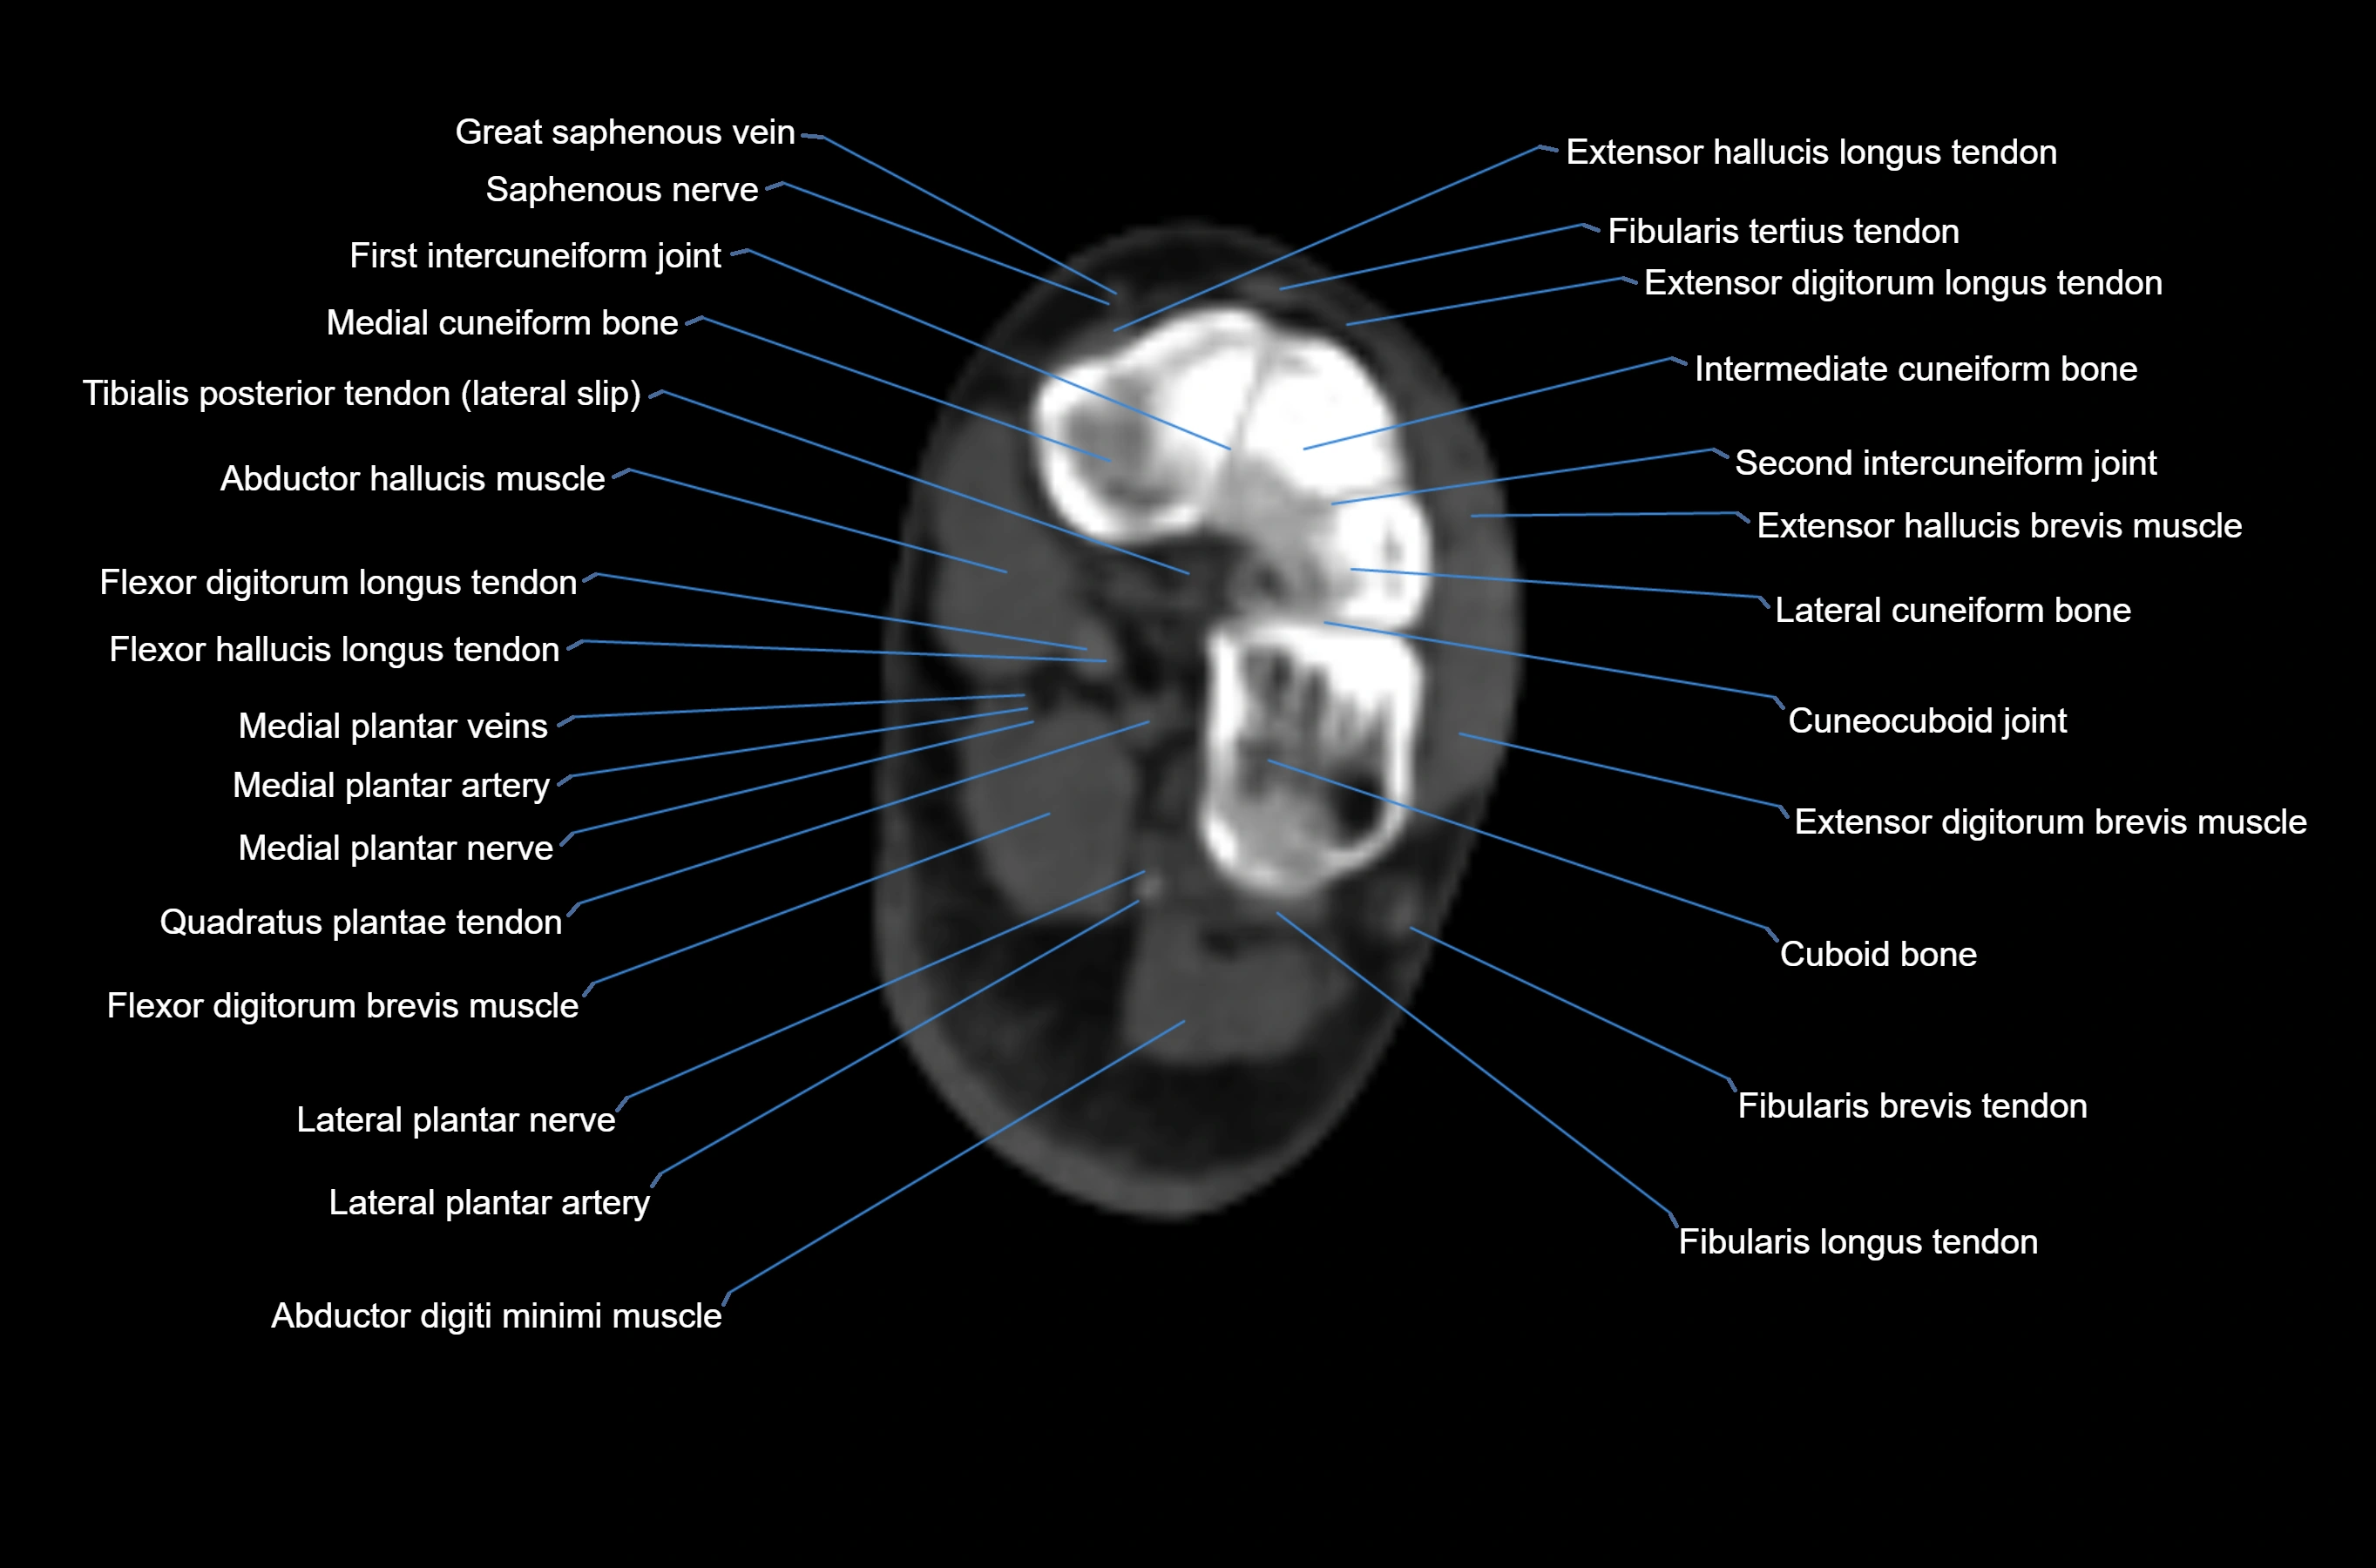

MRI image

CT image